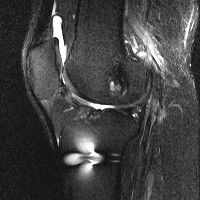

무릎 mri 간단히 봐주실 수 있으시나요 ㅠㅠ

안녕하세요 8년전 십자인대 수술하고 최근 무리한 운동에 무릎 불편감이 생겨서

mri 찍었습니다.

진단결과는 첫 찍은 병원에서 활액막염 이라는 진단을 받았습니다. 혹시 봐주실 수 있으실까요?

올라온 MRI가 단편적이라서 정확한 진단에 어려움이 있지만 십자인대에는 큰 이상이 있지는 않은것 같으며, 무릎관절내 물이 있는 것으로 보아 활액막염의 진단이 맞을 것 같습니다.

하지만 단편적인 영상이기 때문에 촬영병원에서 정확한 판독지 등을 받으시는 것이 좋겠습니다.